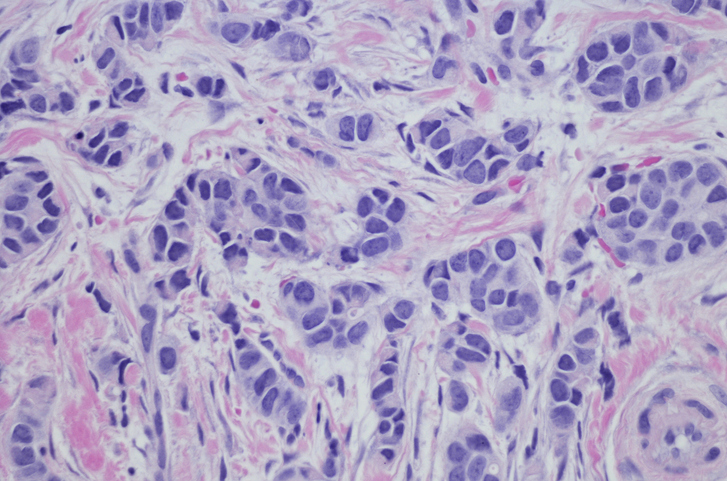

A study has uncovered trends in the incidence of the breast cancer subtype invasive lobular carcinoma.

In a study published in Cancer, investigators used data from the National Program of Cancer Registries and the Surveillance, Epidemiology and End Results Program to analyze the incidence rates of invasive lobular carcinoma.

The investigators found that the rates of invasive lobular carcinoma increased by about 3% per year from 2012 to 2021. The cancer type accounted for about 11% of invasive breast cancer cases between 2017 and 2021 and was more common among patients aged 65 years and older.

The investigators concluded that differentiating invasive lobular carcinoma from other invasive breast cancers may be critical to identifying the most effective treatment strategies and improving patient outcomes.